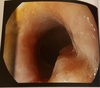

Kissing ulcers no terço médio do esôfago devido a

Nimesulida (na impressão aortica)